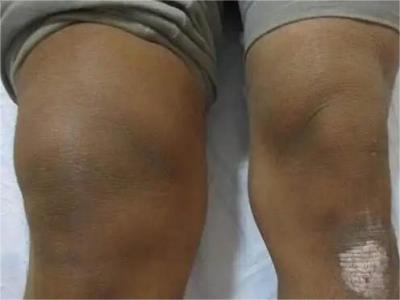

膝关节骨质增生症状图片

4、关节反复肿胀:积液多于不严重的外伤或轻度扭伤后引起关节肿胀积液,疼痛,关节周围压痛,膝关节肌肉痉挛。休息1-2个月后症状可自然消退,可以很长时间没有症状,但可因轻微外伤而反复发作,由于股四头肌无力或因疼痛,膝关节可出现“闪失”现象。

5、关节畸形:病情逐步发展,膝关节出现内翻或外翻畸形,关节骨缘增大。关节主动及被动活动范围逐步减小,关节疼痛转重,在走平路及站立时也引起疼痛感。关节韧带松弛出现关节不稳感,有些病人不能完全伸直膝关节,严重者则膝关节呈屈曲挛缩畸形。开始活动时疼痛加重,休息后缓解,以后可变为持续性疼痛。